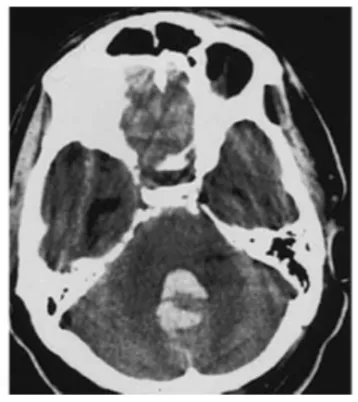

急诊头颅CT检查结果显示:第四脑室内出血。进一步行脑血管造影后发现,此次出血的"元凶"是位于左侧小脑后下动脉(PICA)的一枚动脉瘤。

王女士的动脉瘤位置尤为特殊。小脑后下动脉承担着为小脑、延髓等关键结构供血的重要职责,该部位的动脉瘤在临床上本就极为罕见,仅占所有颅内动脉瘤的0.5%至3%,但其凶险程度不容小觑——一旦破裂,出血往往集中汇入第四脑室,发病急骤、进展迅速,救治窗口极为有限。